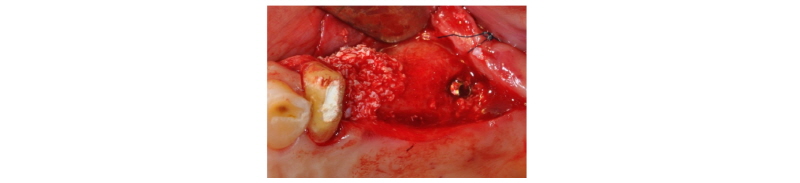

57세의 여성 환자로 기존 브릿지 보철 수복물(#24-27)의 상악 좌측 제 2대구치의 심한 우식으로 인해 내원하여 해당 치아를 발거하였다(Fig. 1). 상악 좌측 제 1 소구치는 근관치료를 시행한 후 보철 수복하기로 하였고 기존 pontic 부위였던 좌측 제 2 소구치와 발거된 제 2 대구치 부위에 #25i, #27i 2개의 임플란트 식립을 통한 브릿지 보철 수복물을 계획하였다(Fig. 2). 기존 pontic으로 유지되었던 좌측 제 2 소구치 부위는 치조제의 심한 수평적 치조골 흡수를 구강 내 임상검사를 통해 확인할 수 있었다. 전층 판막 형성후 상악 좌측 제 2 소구치 부위의 치조정 폭경은 약 2 mm 정도로 측정되었다(Fig. 3, 4). 치조골의 구개측에 약 1 mm의 치조골이 남도록 high speed carbide round bur를 이용하여 치조정에 horizontal intraosseous groove를 형성하였고 협측골의 근심, 원심측에 2개의 vertical intraosseous groove를 형성하였다(Fig. 5). Chisel과 ridge spreader drill (RS kit, Dentium, Korea)을 이용하여 점차적으로 협측 골판을 구개측으로부터 분리시켰다(Fig. 6). Osteotome을 이용, 식립 깊이까지 적용하여 임플란트 식립 부위를 형성하였고 Ø4.3 × 10 mm (Implantium, Dentium, Korea) 임플란트를 식립하였다(Fig. 7). 발치 후 치유된 상악 좌측 제 2 대구치 부위는 상악동 거상술(수직 접근법)을 시행, 골이식을 한 후 4.8 × 10 mm (Implantium, Dentium, Korea)를 식립하였다(Fig. 8). 이후 이종골 이식재(Bio-Oss®, Geistlich, Switzerland)를 식립된 임플란트와 협,구개 측 치조골판 사이의 gap과 협측골판 상방에 적용하고 흡수성 교원질 차폐막(Bio-Gide®, Geistlich, Switzerland)로 피개한 다음 감장절개를 통해 장력없이 봉합하였다(Fig. 9-11). 이후 구강 내 검사 및 방사선 검사를 통해 수술부위 치유상태를 확인하였고 특이한 임상적 소견없이 정상적으로 잘 치유되었다(Fig. 12). 약 3개월 10일 정도의 치유기간 후 이차수술을 시행하였다(Fig. 13). 판막 거상 후 치조제 분할술을 시행하였던 상악 좌측 제 2 소구치 부위에 잘 형성된 신생 골양조직이 관찰되었다(Fig. 14). 상악 좌측 제 2 소구치 부위와 상악 좌측 제 2 구치 부위에 치유지대주를 장착하였고 상악 좌측 제 1 대구치 부위에 추가적으로 임플란트를 1회법으로 식립하였다(Fig. 15). 이차수술 이후 정상적으로 치유가 진행되어 약 2개월 후 최종 보철물 수복을 하였다(Fig. 16, 17). 약 1년 정도의 follow-up시 구강 내 검사와 방사선 검사를 통해서 임플란트 주위 연조직과 변연골이 잘 유지되고 있음을 확인하였다(Fig. 18).

Fig. 23. Ridge spreading with chisel and spreader drill. |